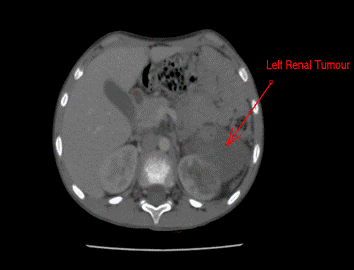

Após a quimioterapia, foi evidenciada resposta satisfatória em relação ao tumor e sua invasão vascular (Figura 2). Foram indicadas nefrectomia radical esquerda, cavectomia e linfadenectomia retroperitoneal pela equipe de cirurgia pediátrica.

Figura 2. Tumor renal esquerda pós-quimioterapia